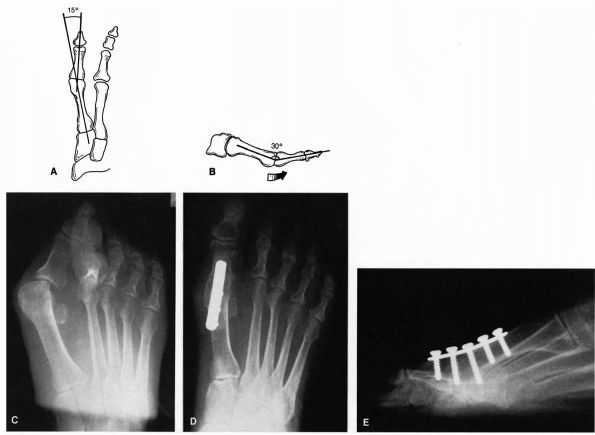

![]() |

FIGURE 21-10. Arthrodesis of the metatarsophalangeal joint. Proper alignment of the arthrodesed joint is 15° of valgus (A) and 30° of dorsiflexion (B)

excellent procedure for patients who have severe deformity or

significant arthroses (grade 3 hallux rigidus). Arthrodesis is also

useful for patients who have failed a previous cheilectomy and as a

salvage procedure for a failed bunion operation. The optimal

positioning of the arthrodesis is 15° of valgus and 10 to 15° of

dorsiflexion in relation to the plantar aspect of the foot (or 25 to

30° of dorsiflexion in relation to the first metatarsal shaft, which is

inclined in a plantar direction about 20°) (Figure 21-10).

After arthrodesis, the patient can be ambulated in a postoperative

wooden shoe until the arthrodesis site is solid, which is usually about

10 to 12 weeks after surgery. The main complications of arthrodesis are

malalignment of the arthrodesis site and nonunion, although uncommon.

If sufficient valgus and dorsiflexion is not placed into the

arthrodesis at the time of surgery, excessive wear on the

interphalangeal joint occurs—a potential problem.